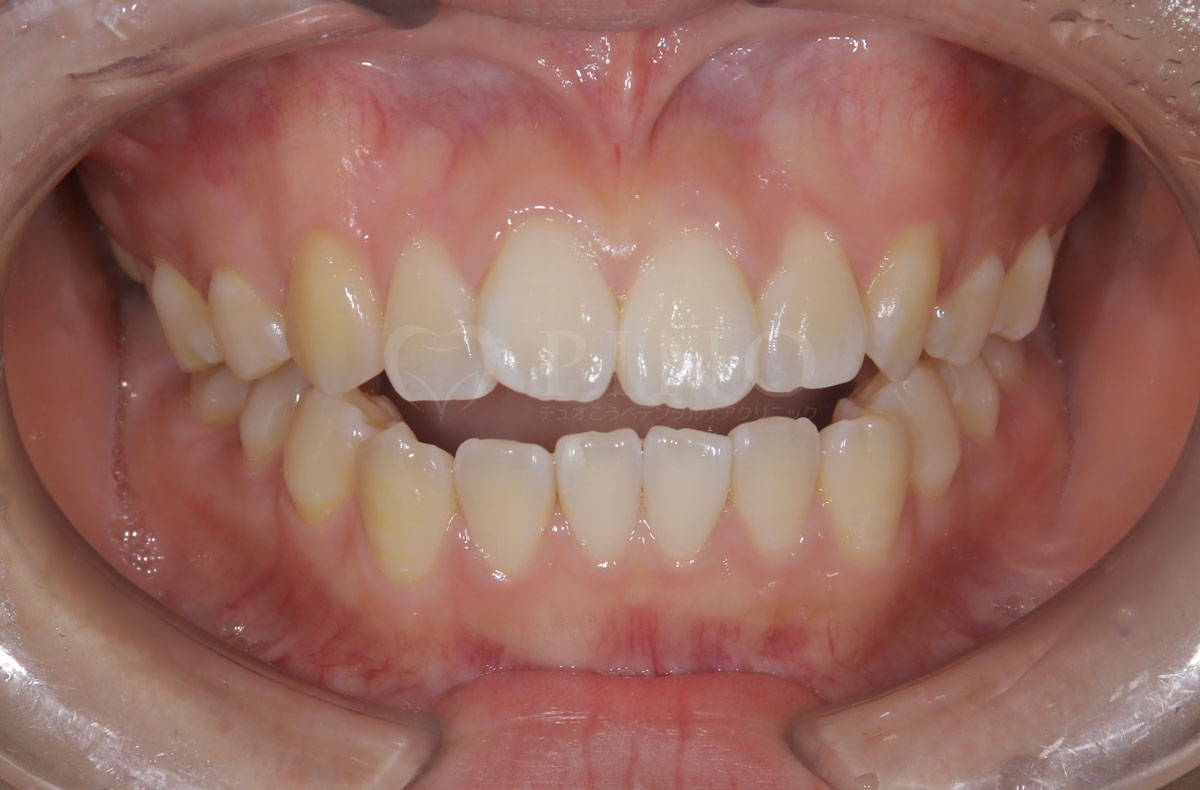

症例5:前歯が噛み合わないのが気になる(20代女性)

主訴 前歯が噛み合わないのが気になる 診断名 開咬 治療方法 マウスピース全顎矯正 抜歯 なし オルソパルス なし 治療期間 1年2ヶ月 費用 749,000円 副作用・注意点 非抜歯での治療のため、歯と歯の間をわずかに削る必要がある、矯正後の後戻りを防ぐためリテーナーの使用が必要となる 備考 奥歯に噛み合わせ不良がない場合、部分矯正が適応となる -